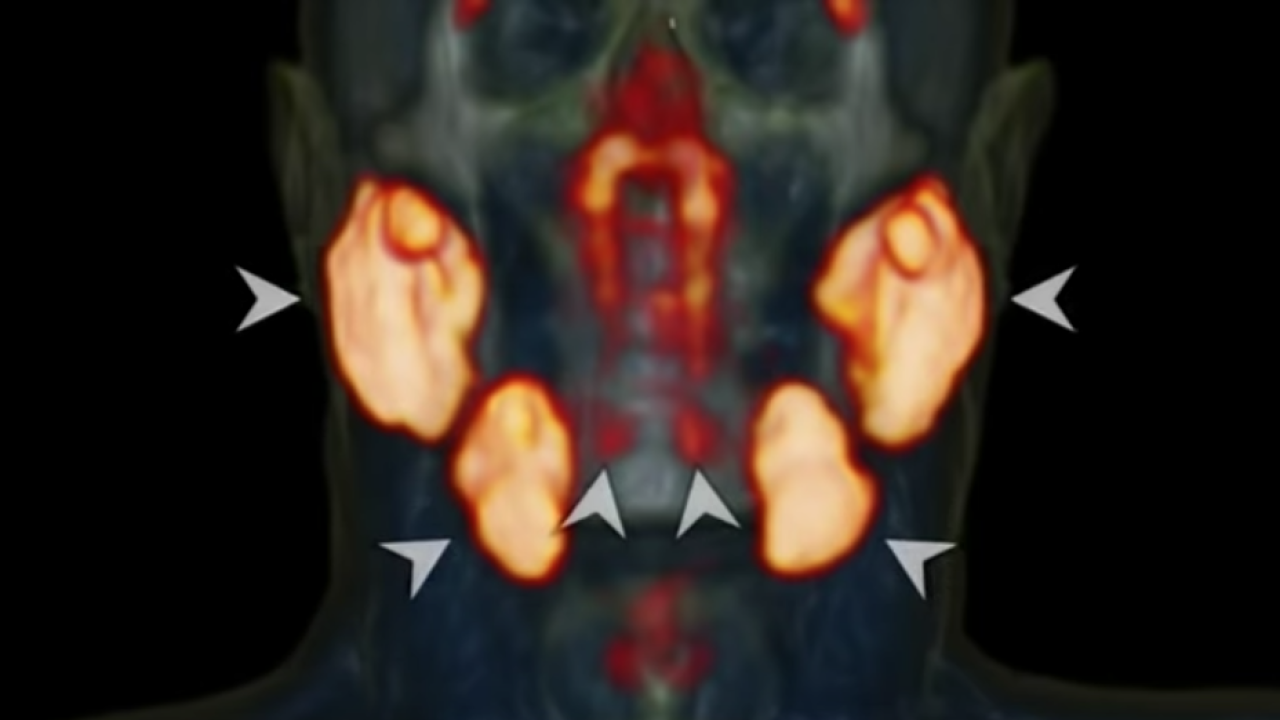

Hollanda Kanser Enstitüsündeki onkologlar, baş ve boyun kanserli hastalar üzerinde yaptıkları araştırmanın bir parçası olarak yeni bir tür tarama kullanıyorlardı. Prostat kanserinin vücutta yayılmasını izlemenin etkili bir yolu olduğu gösterilen prostata özgü zar antijen ligandları (PSMA PET/CT) taramaları ile pozitron emisyon tomografisi/bilgisayarlı tomografi kullandılar. Hastalara, taramadan önce parlak bir şekilde parlayarak hastadaki tümörleri vurgulayan radyoaktif glikoz enjekte edildi.

Ancak ekip, bu taramayı hastalar üzerinde kullanırken kafanın iki bölgesinin beklenmedik bir şekilde aydınlandığını fark etti. Hastaları taramaya devam ederken, aynı alanın aydınlandığını fark ettiler.  Taranan 100 kişinin hepsinin parlak noktaları olduğu ortaya çıktı. Bu bir anormallik değildi, potansiyel olarak tamamen yeni bir organdı.

Radyoterapi ve Onkoloji dergisinde açıklanan yeni keşif,  nazofarenksin arkasında konumlanmış bir dizi tükürük bezidir. Bunlar ağırlıklı olarak çoklu drenaj kanallarına sahip müköz bezlerdir.

Ekip bulgularını Amsterdam UMC'deki meslektaşlarıyla kadavra kullanarak doğruladı ve şimdi insanlığın en yeni organını bulundukları yere atıfta bulunarak "tüberyal bezler" olarak adlandırdı. Bezlerin, radyasyon alan hastalarda disfaji (yutma güçlüğü) dahil olmak üzere komplikasyonların bir nedeni olabileceğini ve bunları bilmenin onkologların potansiyel komplikasyonları önlemek için bu alandan kaçınmasına yardımcı olabileceğini öne sürüyorlar.